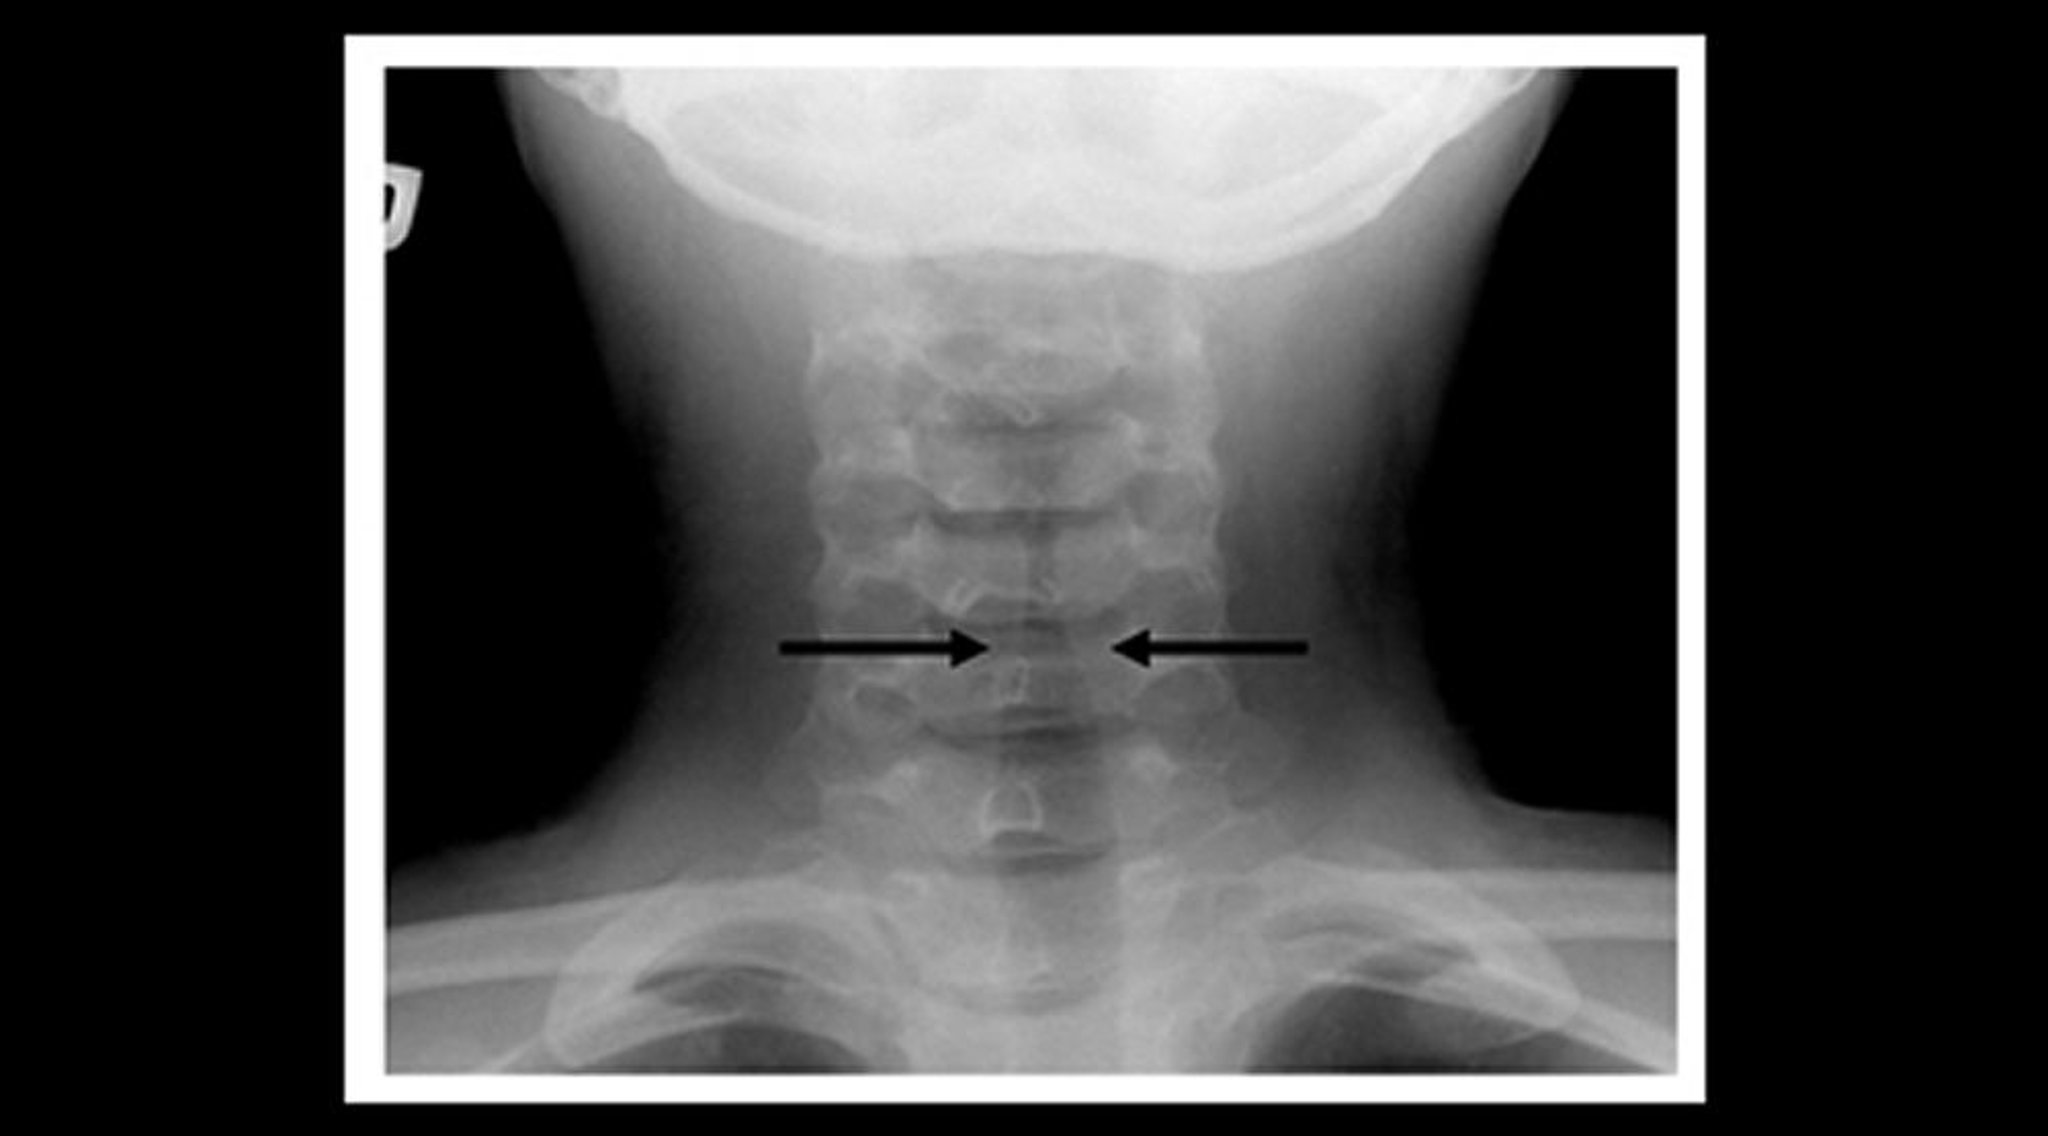

Рентгенография у ребенка с крупом (корональная проекция)

При рентгенологическом исследовании мягких тканей шеи у ребенка с крупом выявлено постепенное сужение эндотрахеальной трубки ниже складок голосовой щели (симптом "шпиля"– обозначен стрелкой) и расширение фарингальных просветов.

Image courtesy of John McBride, MD.